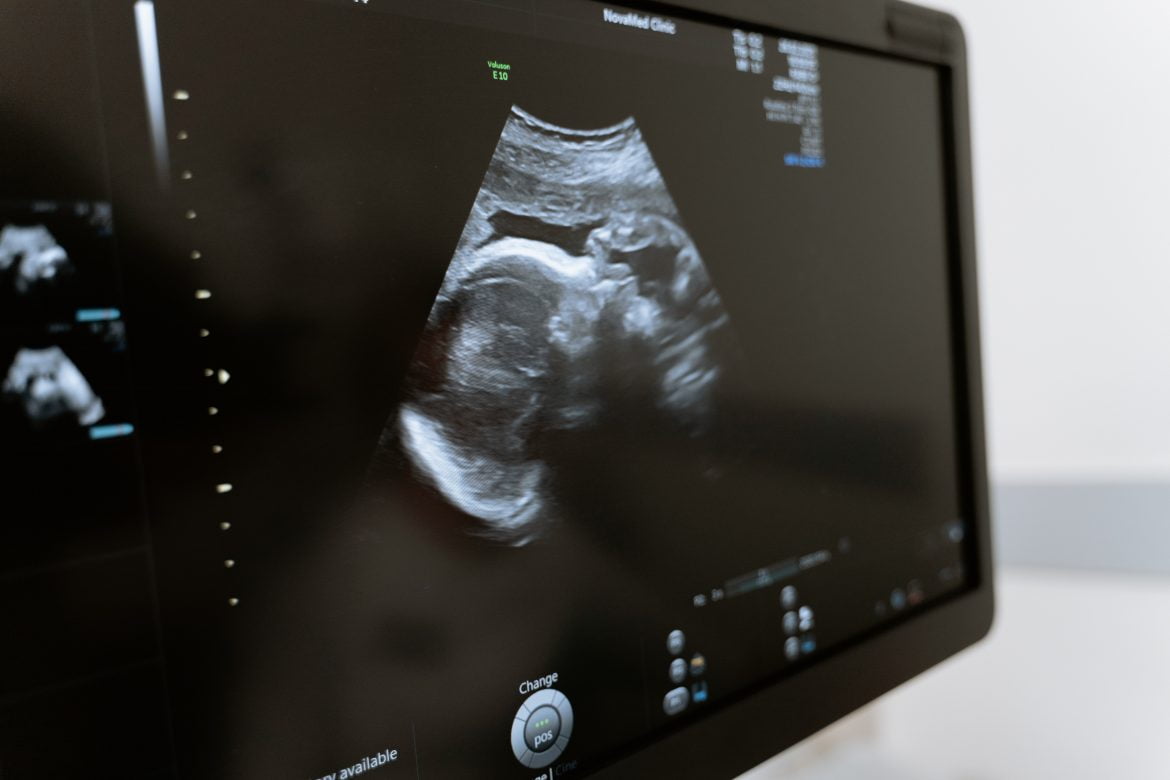

La mujer se desempeñaba como supervisora de área administrativa. El 28 de julio de 2021, en el Servicio de Ginecología y Obstetricia del hospital le diagnosticaron embarazo con amenaza de aborto, razón por la cual le otorgaron incapacidad; posteriormente, solicitó vacaciones del primer periodo anual y se reincorporó sus actividades laborales hasta el 7 de septiembre del miso año.